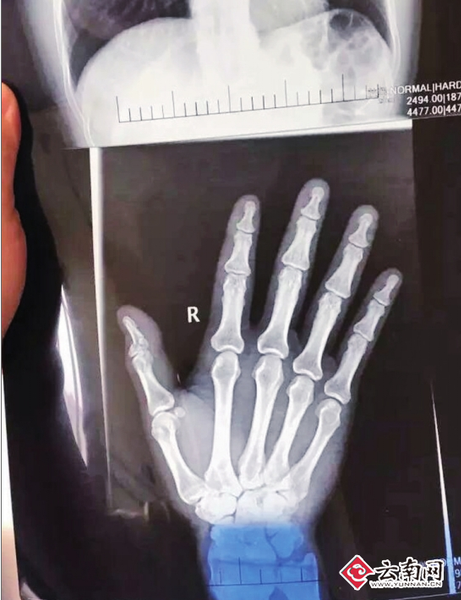

被打教师的女儿在网络上晒出受伤照片

黄敏说,被打后,他立即报了警。除身上多处软组织挫伤外,伤得最严重的是右手大拇指粉碎性骨折,一掌骨骨折。他到云南省第三人民医院住了7天院,医生说无法手术,只能用夹板固定,也不吃药,待其自然修复,至少要3个月以上,右手大拇指还有可能伤残。